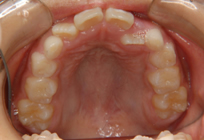

上顎前突(出っ歯)10歳男子

治療前

出っ歯治療後

①主訴:出っ歯を治したい

②診断名あるいは主な症状:上顎前歯の前方への突出

③年齢:10歳

④治療に用いた主な装置:ライトワイヤー +(機能的矯正装置)

⑤抜歯部位:非抜歯

⑥治療期間:約1年半~2年

⑦治療費:検査:38,500円

基本矯正費用:440,000円~

調整料:6,600円 (ひと月に1回)

⑧リスクと副作用:治療開始後数日は噛むときに痛みがあります。

虫歯予防のため適切な歯磨きが必要

装置が破損することがあるため、その時は連絡をすること

後戻り防止のため、保定装置の装着が必要である。

第2期(永久歯列期)での仕上げの治療が必要になる場合もある